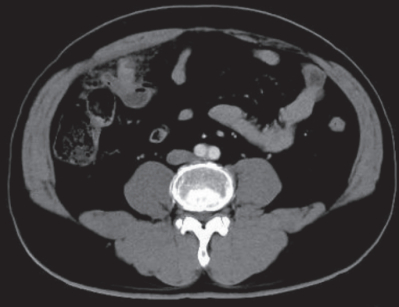

血液所見:赤血球 486 万、Hb 15.0 g/dL、Ht 44 %、白血球 18,000(好中球82 %、好酸球 1 %、好塩基球 1 %、単球 6 %、リンパ球 10 %)、血小板 26 万、PTINR 0.9(基準 0.9~1.1)。 血液生化学所見: 総蛋白 8.1 g/dL、 アルブミン5.1 g/dL、総ビリルビン 1.2 mg/dL、AST 23 U/L、ALT 30 U/L、LD 166 U/L(基準 120~245)、ALP 39 U/L(基準 38~113)、γ-GT 25 U/L(基準 8 ~50)、アミラーゼ 44 U/L(基準 37~160)、CK 64 U/L(基準 30~140)、尿素窒素 17 mg/dL、クレアチニン 1.2mg/dL、 尿酸 6.4 mg/dL、 血糖 109 mg/dL、Na 140 mEq/L、K 3.9 mEq/L、Cl 101 mEq/L、Ca 9.8 mg/dL。CRP 19 mg/dL。 腹部造影 CTを別に示す。

この患者の治療法で適切なのはどれか。

a. 緊急手術